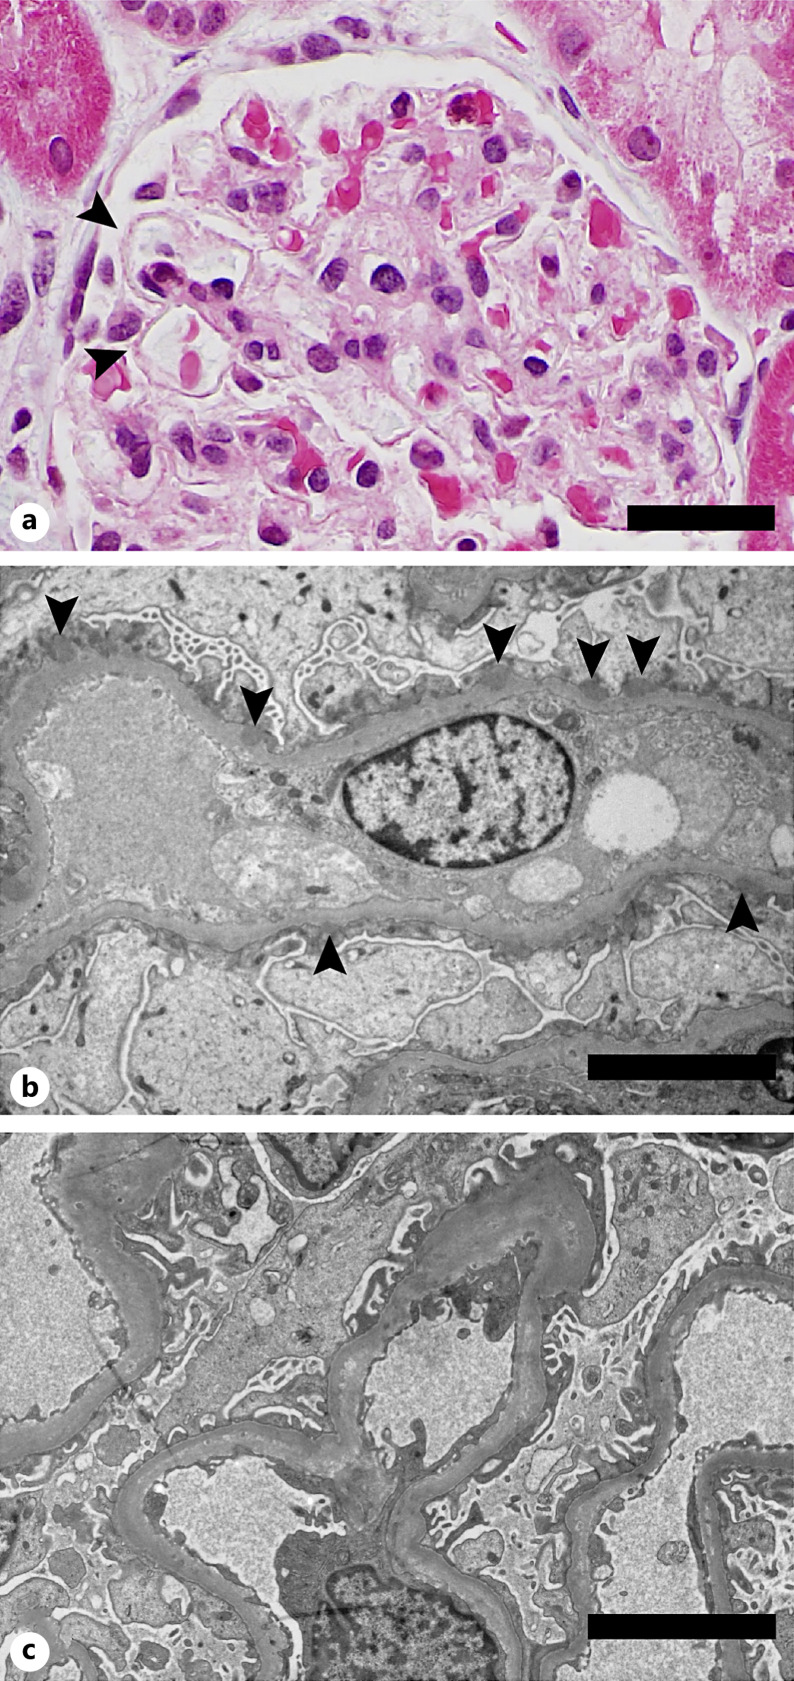

Case presentation: Here, we present 2 patients with defects in immune tolerance mechanisms that developed MCD associated with anti-nephrin antibodies. The first patient had a pathogenic deletion in FOXP3, leading to reduced regulatory T cells. Serum could not be obtained from this patient during the active phase of MCD to directly establish the presence of anti-nephrin antibodies. However, this patient demonstrated IgG dusting over podocyte cell bodies by immunofluorescence microscopy, as well as colocalization of IgG with nephrin in confocal microscopy. The second patient developed MCD in the context of immune checkpoint inhibitor treatment for metastatic carcinoma. Anti-nephrin antibodies were detected in this patient during active disease. The patient's kidney biopsy also showed evidence of binding of anti-nephrin antibodies within the glomeruli.